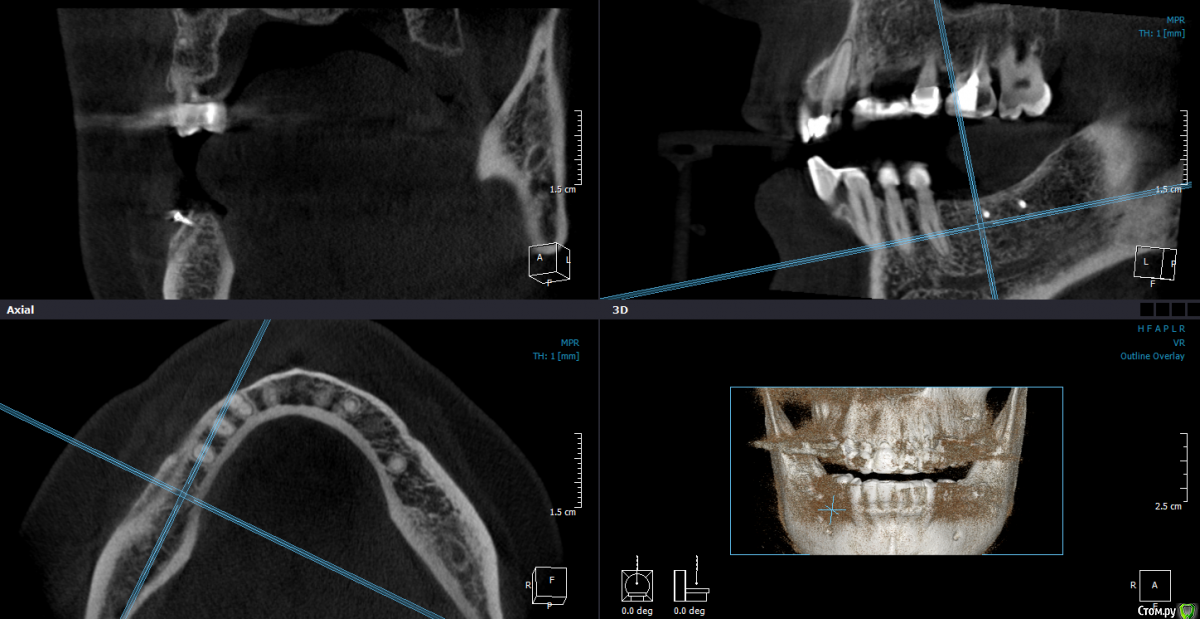

Mane Опубликовано 22 декабря, 2014 Поделиться Опубликовано 22 декабря, 2014 в целом хорошо. но нет деталей где я смогу понять что качественно отработали: 1) кт срезы до и после с замерами чтоб было понятно на сколько нарастили 2)кт срезы с установленными имплантами чтоб было понятно какие болты удалось установить и стало чтоб всем понятно для чего наращивали - ведь вы растили в высоту и в ширину. 3) фото на этапе установленных имплантов - соотношение платформы импланта и уровня кости - заглубили или нет - если да то насколько. Ориентировались ли на будущий зенит зуба. мне понравилось. но чуйка что есть гиперлечение - думаю можно было болты и костную пластику совместить. Растить по высоте я скорее всего бы не стал. 1 Ссылка на комментарий

SDC Опубликовано 22 декабря, 2014 Поделиться Опубликовано 22 декабря, 2014 Через 5 месяцев...Мне не понравилось просветление в 3 квадранте. Крутили КТ? Что это? Ссылка на комментарий

Dantist55 Опубликовано 22 декабря, 2014 Автор Поделиться Опубликовано 22 декабря, 2014 в целом хорошо. но нет деталей где я смогу понять что качественно отработали: 1) кт срезы до и после с замерами чтоб было понятно на сколько нарастили 2)кт срезы с установленными имплантами чтоб было понятно какие болты удалось установить и стало чтоб всем понятно для чего наращивали - ведь вы растили в высоту и в ширину. 3) фото на этапе установленных имплантов - соотношение платформы импланта и уровня кости - заглубили или нет - если да то насколько. Ориентировались ли на будущий зенит зуба. мне понравилось. но чуйка что есть гиперлечение - думаю можно было болты и костную пластику совместить. Растить по высоте я скорее всего бы не стал.КТ посмотрю позже на работе - я в отпуске.По высоте добавляли чтобы зубы не получились большими.Импланты не заглублял, т.к. у XIVE полированная фаска.Насчет гиперлечения может Вы и правы. Эту работу я сделал сразу после приезда от Кури. 2 Ссылка на комментарий

Dantist55 Опубликовано 22 декабря, 2014 Автор Поделиться Опубликовано 22 декабря, 2014 Мне не понравилось просветление в 3 квадранте. Крутили КТ? Что это?Перед имплантацией крутил-все было норм. Ссылка на комментарий